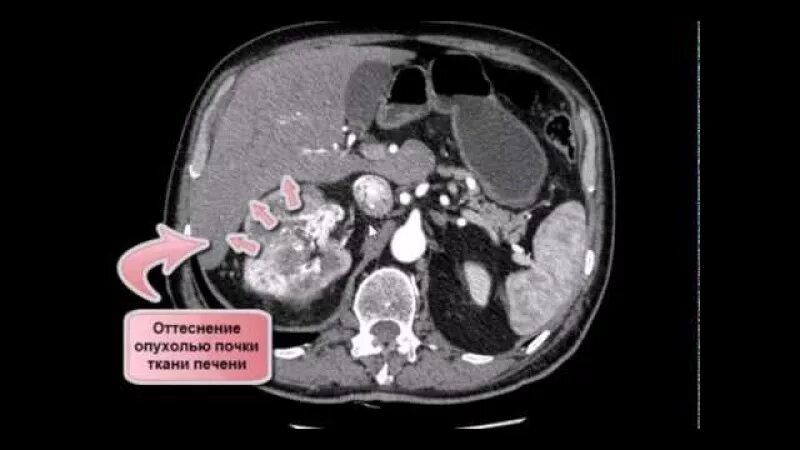

Могут ли метастазы перепутать